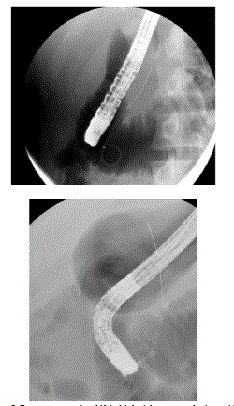

Figure 2. Pancreas stenting (A) in high risk cases and wire guided approaches (B) are technical manoeuvres which minimize the risk of PEP.